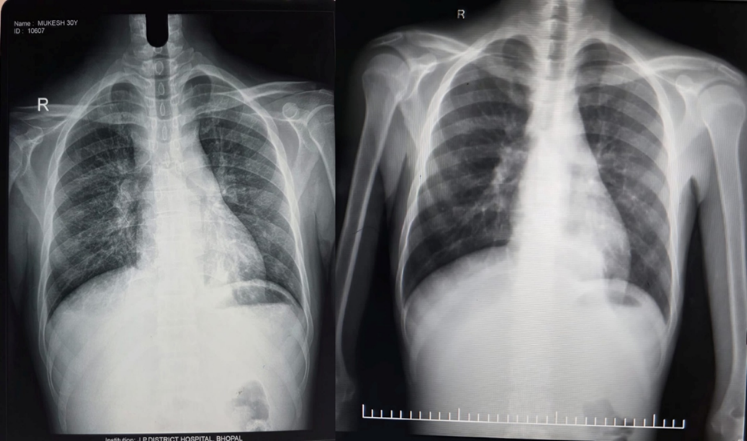

Chest X-ray showing bilateral lower zone opacities with ill-defined margins, consistent with consolidation. No obvious cavitation noted. Post treatment Chest Xray shows improvement.